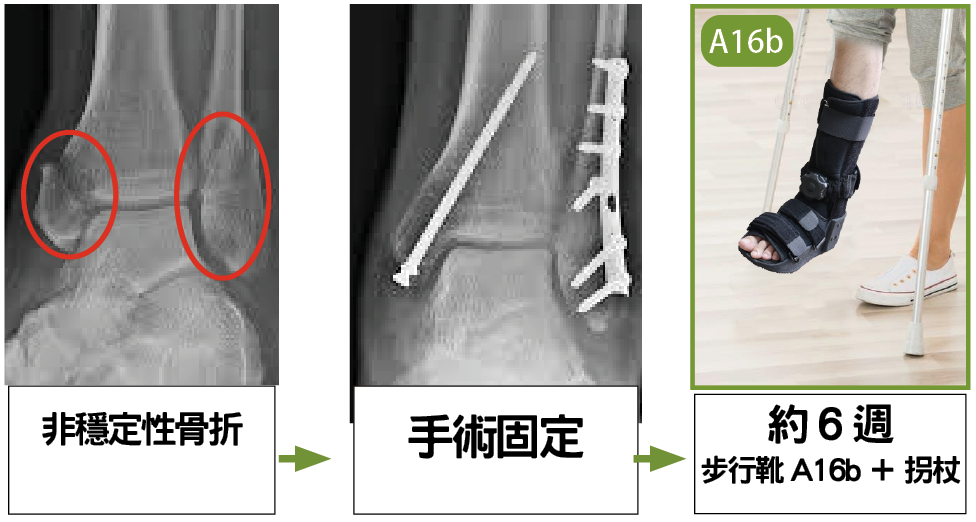

非穩定性足踝骨折

ii. 護具處理非穩定性移位骨折: 手術及術後復康

當患者出現不穩定或移位踝關節骨折時,需要進行手術復位,並使用螺絲和鋼板進行固定。

術後還需進行X 光檢查,以確保復位效果良好。術後6 週,應使用短身步行靴(A16b),同時使用拐杖,從而保護手術傷口和固定足踝,並減輕負重或擺動引起的疼痛,此期間可用拐杖作漸進式負重復康比較安全。